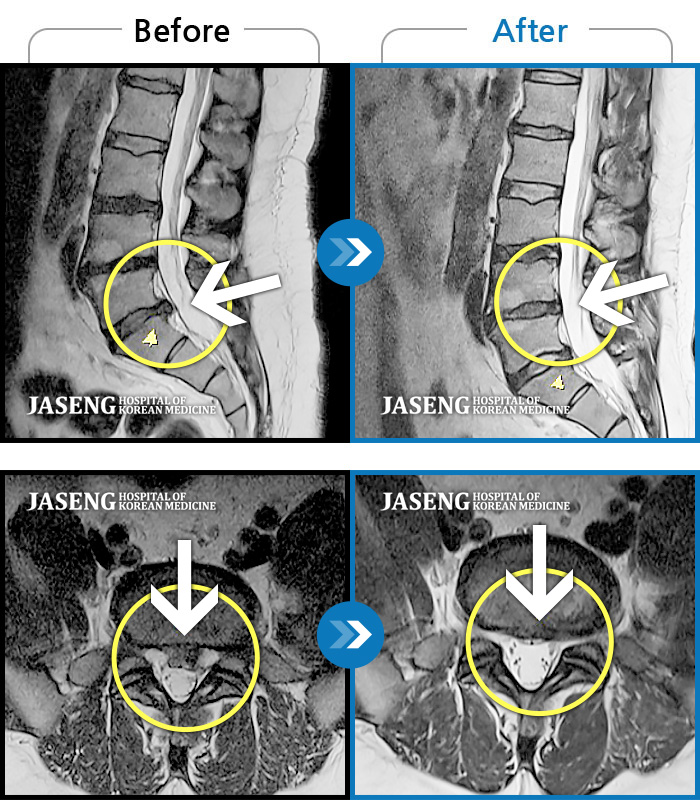

허리디스크

도움받은 사례

광주 · 장영우 원장

양측 허리부터 좌측 다리까지 이어지는 저림과 통증으로 걷기 힘들어 내원하였습니다.

촬영시기

2024.11.22 ~ 2025.05.16

2025.05.30

조회수 285